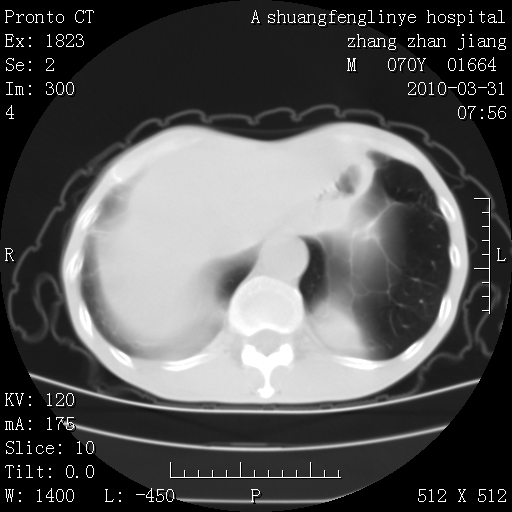

双上肺继发型tb并左上空洞形成,主动脉冠脉钙化。

1)两肺上叶继发性肺结核并左肺上叶空洞形成。2)冠状动脉及主动脉钙化。